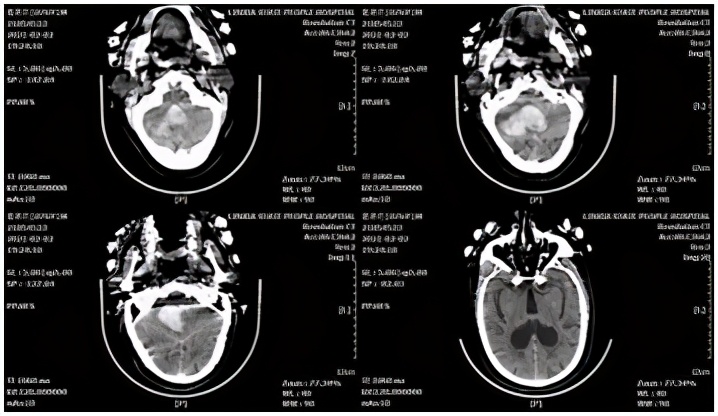

脑叶出血病例,患者女性,61岁。主因"“突发意识障碍、恶心、呕吐5小时”",于2021-02-20收入院。头颅CT示:左侧颞顶叶脑内血肿。

术前CT

术中采用微骨窗入路,保护缺血半暗带,最终 回复 良好。

术后CT